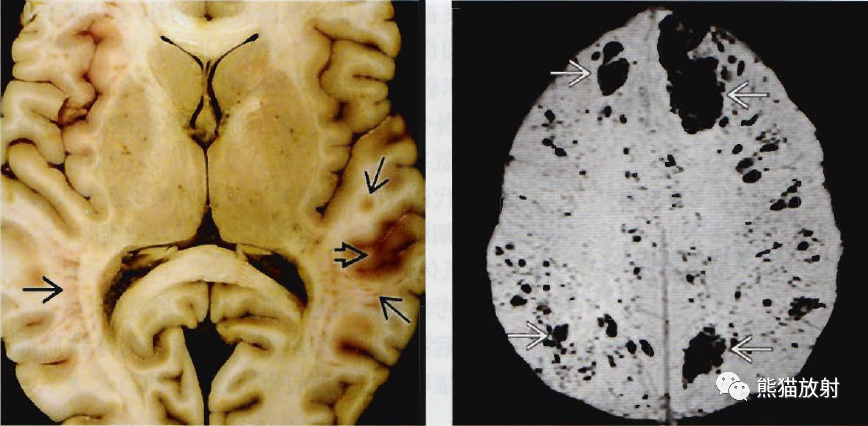

三甲读片丨弥漫性轴索损伤

mr磁敏感加权成像诊断弥漫性轴索损伤